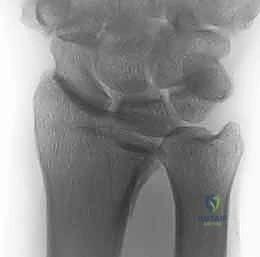

- الأشعة السينية (X-rays):

هي الخطوة الأولى لتقييم الكسر. يتم أخذ صور من زوايا متعددة (أمامية خلفية، جانبية، ومائلة) لتحديد موقع الكسر الأساسي ودرجة الانزياح والتقصير في عظم الكعبرة.

- التصوير المقطعي المحوسب (CT Scan) مع إعادة البناء ثلاثي الأبعاد:

هذا هو المعيار الذهبي الذي يعتمده الدكتور هطيف لجميع كسور المفصل المعقدة. تتيح الأشعة المقطعية رؤية كل شظية عظمية بوضوح تام، وتحديد حجمها، وموقعها، ودرجة تفتت السطح المفصلي بدقة ملليمترية. من خلال إعادة البناء ثلاثي الأبعاد (3D Reconstruction)، يمكن للدكتور هطيف "رؤية" الكسر من جميع الزوايا قبل فتح الجلد، مما يسمح له باختيار الغرسات (الصفائح والمسامير) الدقيقة لكل شظية وتحديد المداخل الجراحية المثلى.